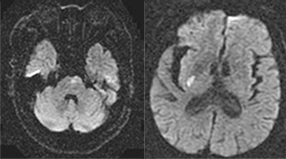

뇌혈관이 막히거나 터지는 질환을 부르는게 뇌졸중이고 그 중 뇌혈관이 막히는게 뇌경색 그리고 뇌혈관이 터지는 것을 뇌출혈이라고 합니다. 뇌졸중은 영구적인 손상이 많다고 하며 증상에 따라 전신이나 육체 일부 기능이 마비되는 등의 극심한 후유증이 남는 무서운 질병입니다 오늘은 뇌경색 초기증상에 대하여 알려드리도록 하겠습니다.

허혈성 뇌졸중은 발생 기전에 따라 대혈관 질환에 의한 뇌경색, 심인성 뇌경색 또는 심인성 뇌경색, 소혈관 질환 또는 틈새 뇌경색, 기타 드문 이유가 되는 것에 의한 뇌경색으로 나누어져요. 에피소드는 일정 기간 동안 증상이 완전히 가라앉는 경우입니다.

허혈성 뇌졸중의 대표적인 이유가 되는 것은 고혈압, 당뇨병, 고지혈증 등으로 인해서 뇌에 혈액을 전달하는 혈관에 동맥경화(동맥경화)가 발생하여 뇌로 가는 혈류를 차단하는 것입니다.